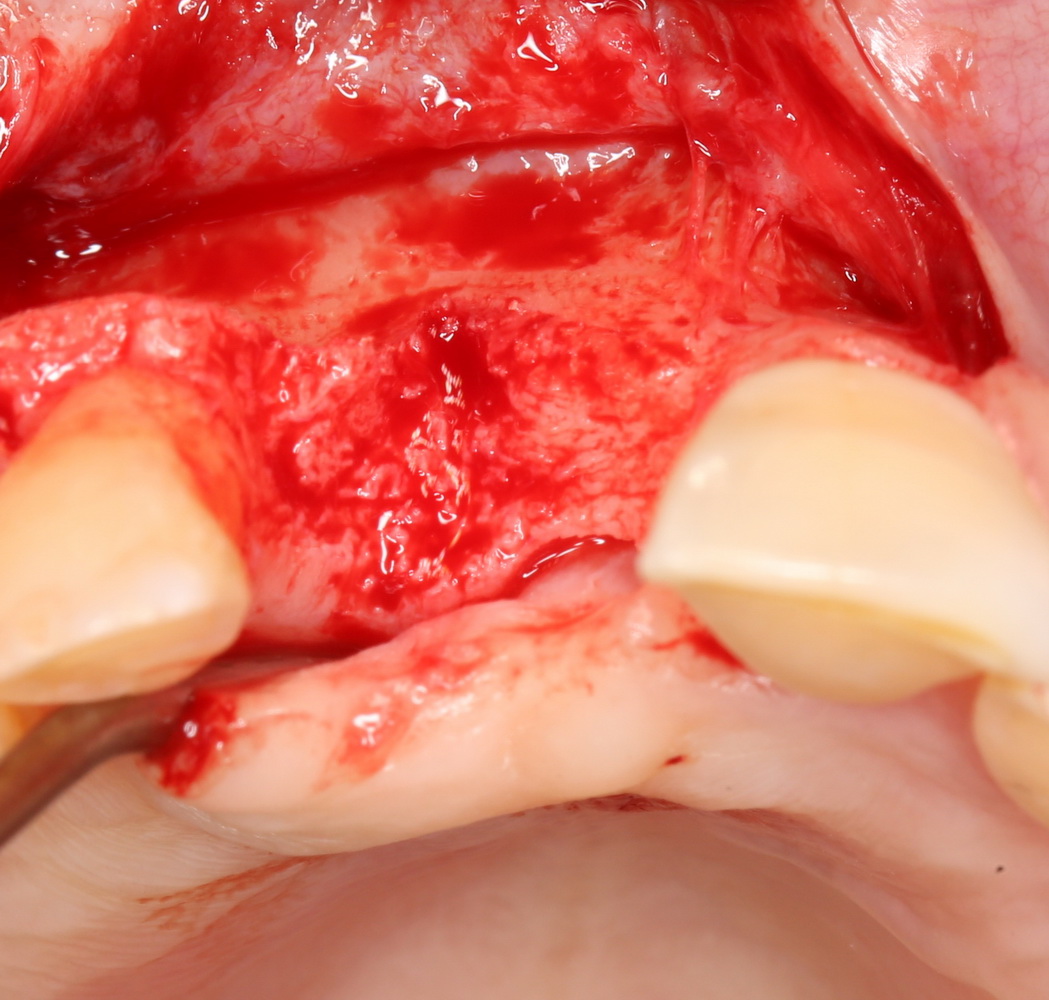

В этом случае остеопластика делается отдельной процедурой. Ее принципы точно те же, но уже без импланта. Например:

Имплантировать в таких условиях — заведомо обрекать себя на хреновый, с точки зрения эстетики и функциональности, результат. Поэтому первым этапом проводим остеопластику. Объем небольшой, использовать в таких объемах костный блок не очень рационально. Воспользуемся аутокостной стружкой и мембраной.

Сначала фиксируется BioGide. Это легко:

Затем укладывается и конфигурируется аутокостная стружка:

Если после этого BioGide намочить физраствором, им легко укрыть получившийся объем:

Для надежности можно зафиксировать пинами: